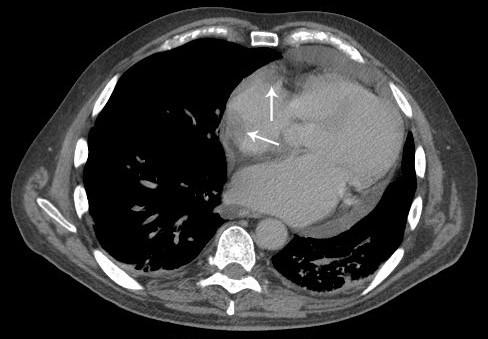

A 71-year-old male with a history of atrial fibrillation, coronary artery disease, pericardial effusion, type-2 diabetes and hypothyroidism presented with 5 weeks of fatigue and 1 day of dizziness. Physical examination was significant for pallor and tachycardia. Laboratory analysis revealed a hemoglobin count of 7.2 g/dl and iron deficiency anemia. The patient was transfused and evaluated by endoscopic ultrasound. A polypoid mass in the gastric cardia was found and later diagnosed as gastric adenocarcinoma (staged as T1N0M0). The pericardial effusion was evaluated with transthoracic echocardiography which showed a 2.0 x 2.7 cm mass associated with the right atrium. Transesophageal echocardiography confirmed the mass but did not reveal constrictive physiology. Whole-body contrast computed tomography failed to demonstrate metastatic disease. Biopsy of the cardiac mass revealed epicarditis without parietal pericardium involvement. Partial gastrectomy was performed to remove the gastric adenocarcinoma.

一名71岁男性,有房颤、冠状动脉疾病、心包积液、2型糖尿病和甲状腺功能减退病史,出现5周疲劳及1天头晕症状。体格检查发现面色苍白和心动过速。实验室分析显示血红蛋白计数为7.2 g/dl,诊断为缺铁性贫血。患者接受输血治疗并接受内镜超声检查。发现胃贲门处有一息肉样肿物,后来诊断为胃腺癌(分期为T1N0M0)。通过经胸超声心动图评估心包积液,结果显示右心房有一个2.0×2.7 cm的肿物。经食管超声心动图证实了该肿物,但未显示缩窄性生理学表现。全身对比计算机断层扫描未发现转移性疾病。心脏肿物活检显示为心外膜炎,未累及壁层心包。患者接受了部分胃切除术以切除胃腺癌。